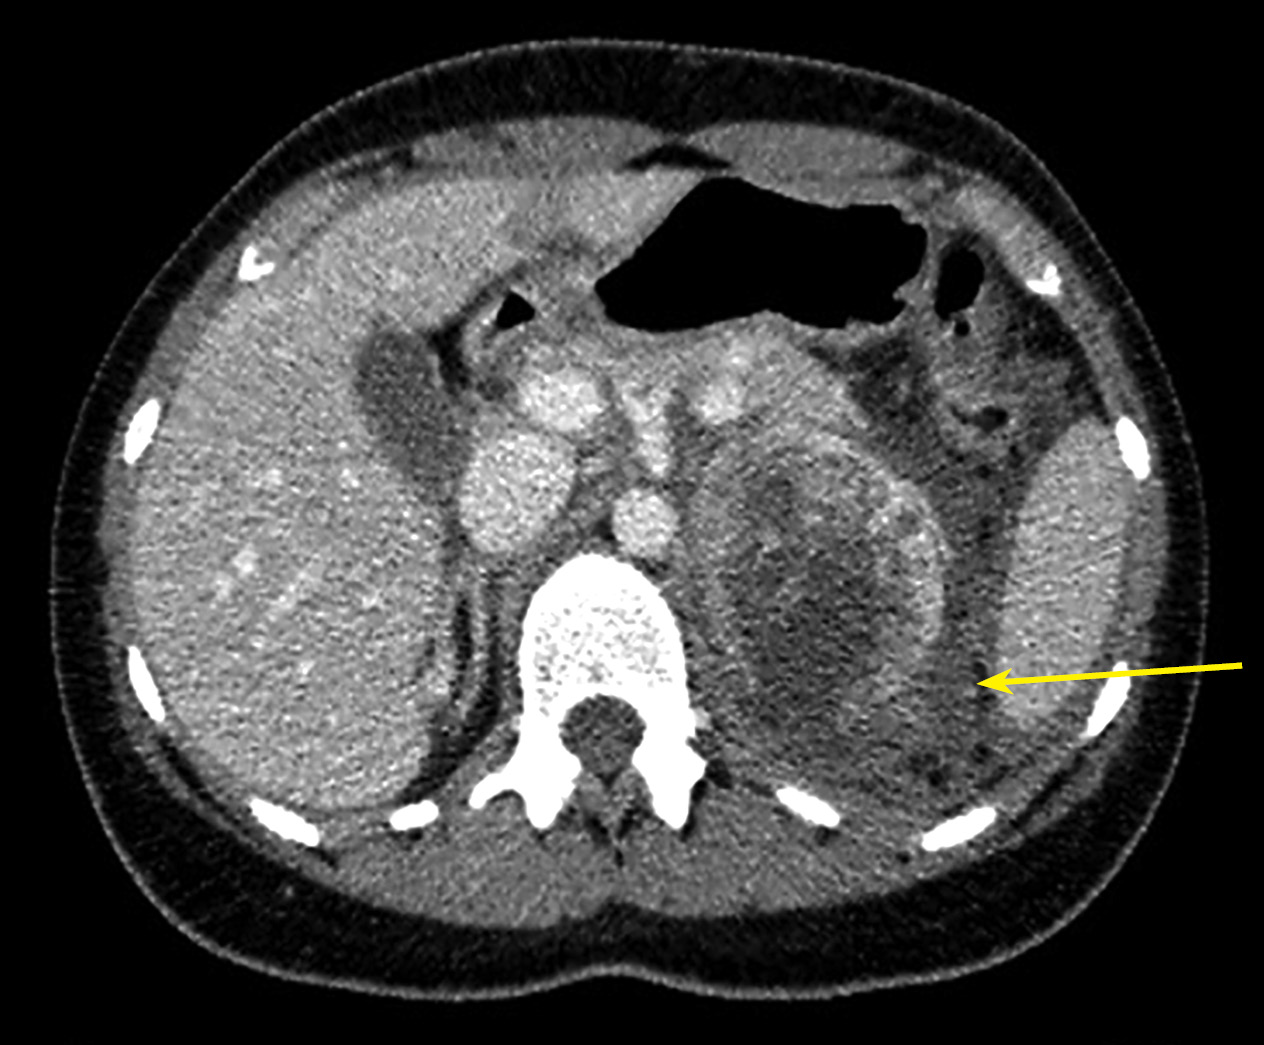

1. Рисунок 1. Пациентка П., 38 лет. МСКТ органов брюшной полости 31.05.2022 г. (венозная фаза), многоузловое образование слева (маркирована стрелкой), смещающее селезенку и сдавливающее левую почку: а) корональная проекция; б) аксиальная проекция; в) сагиттальная проекция. | |